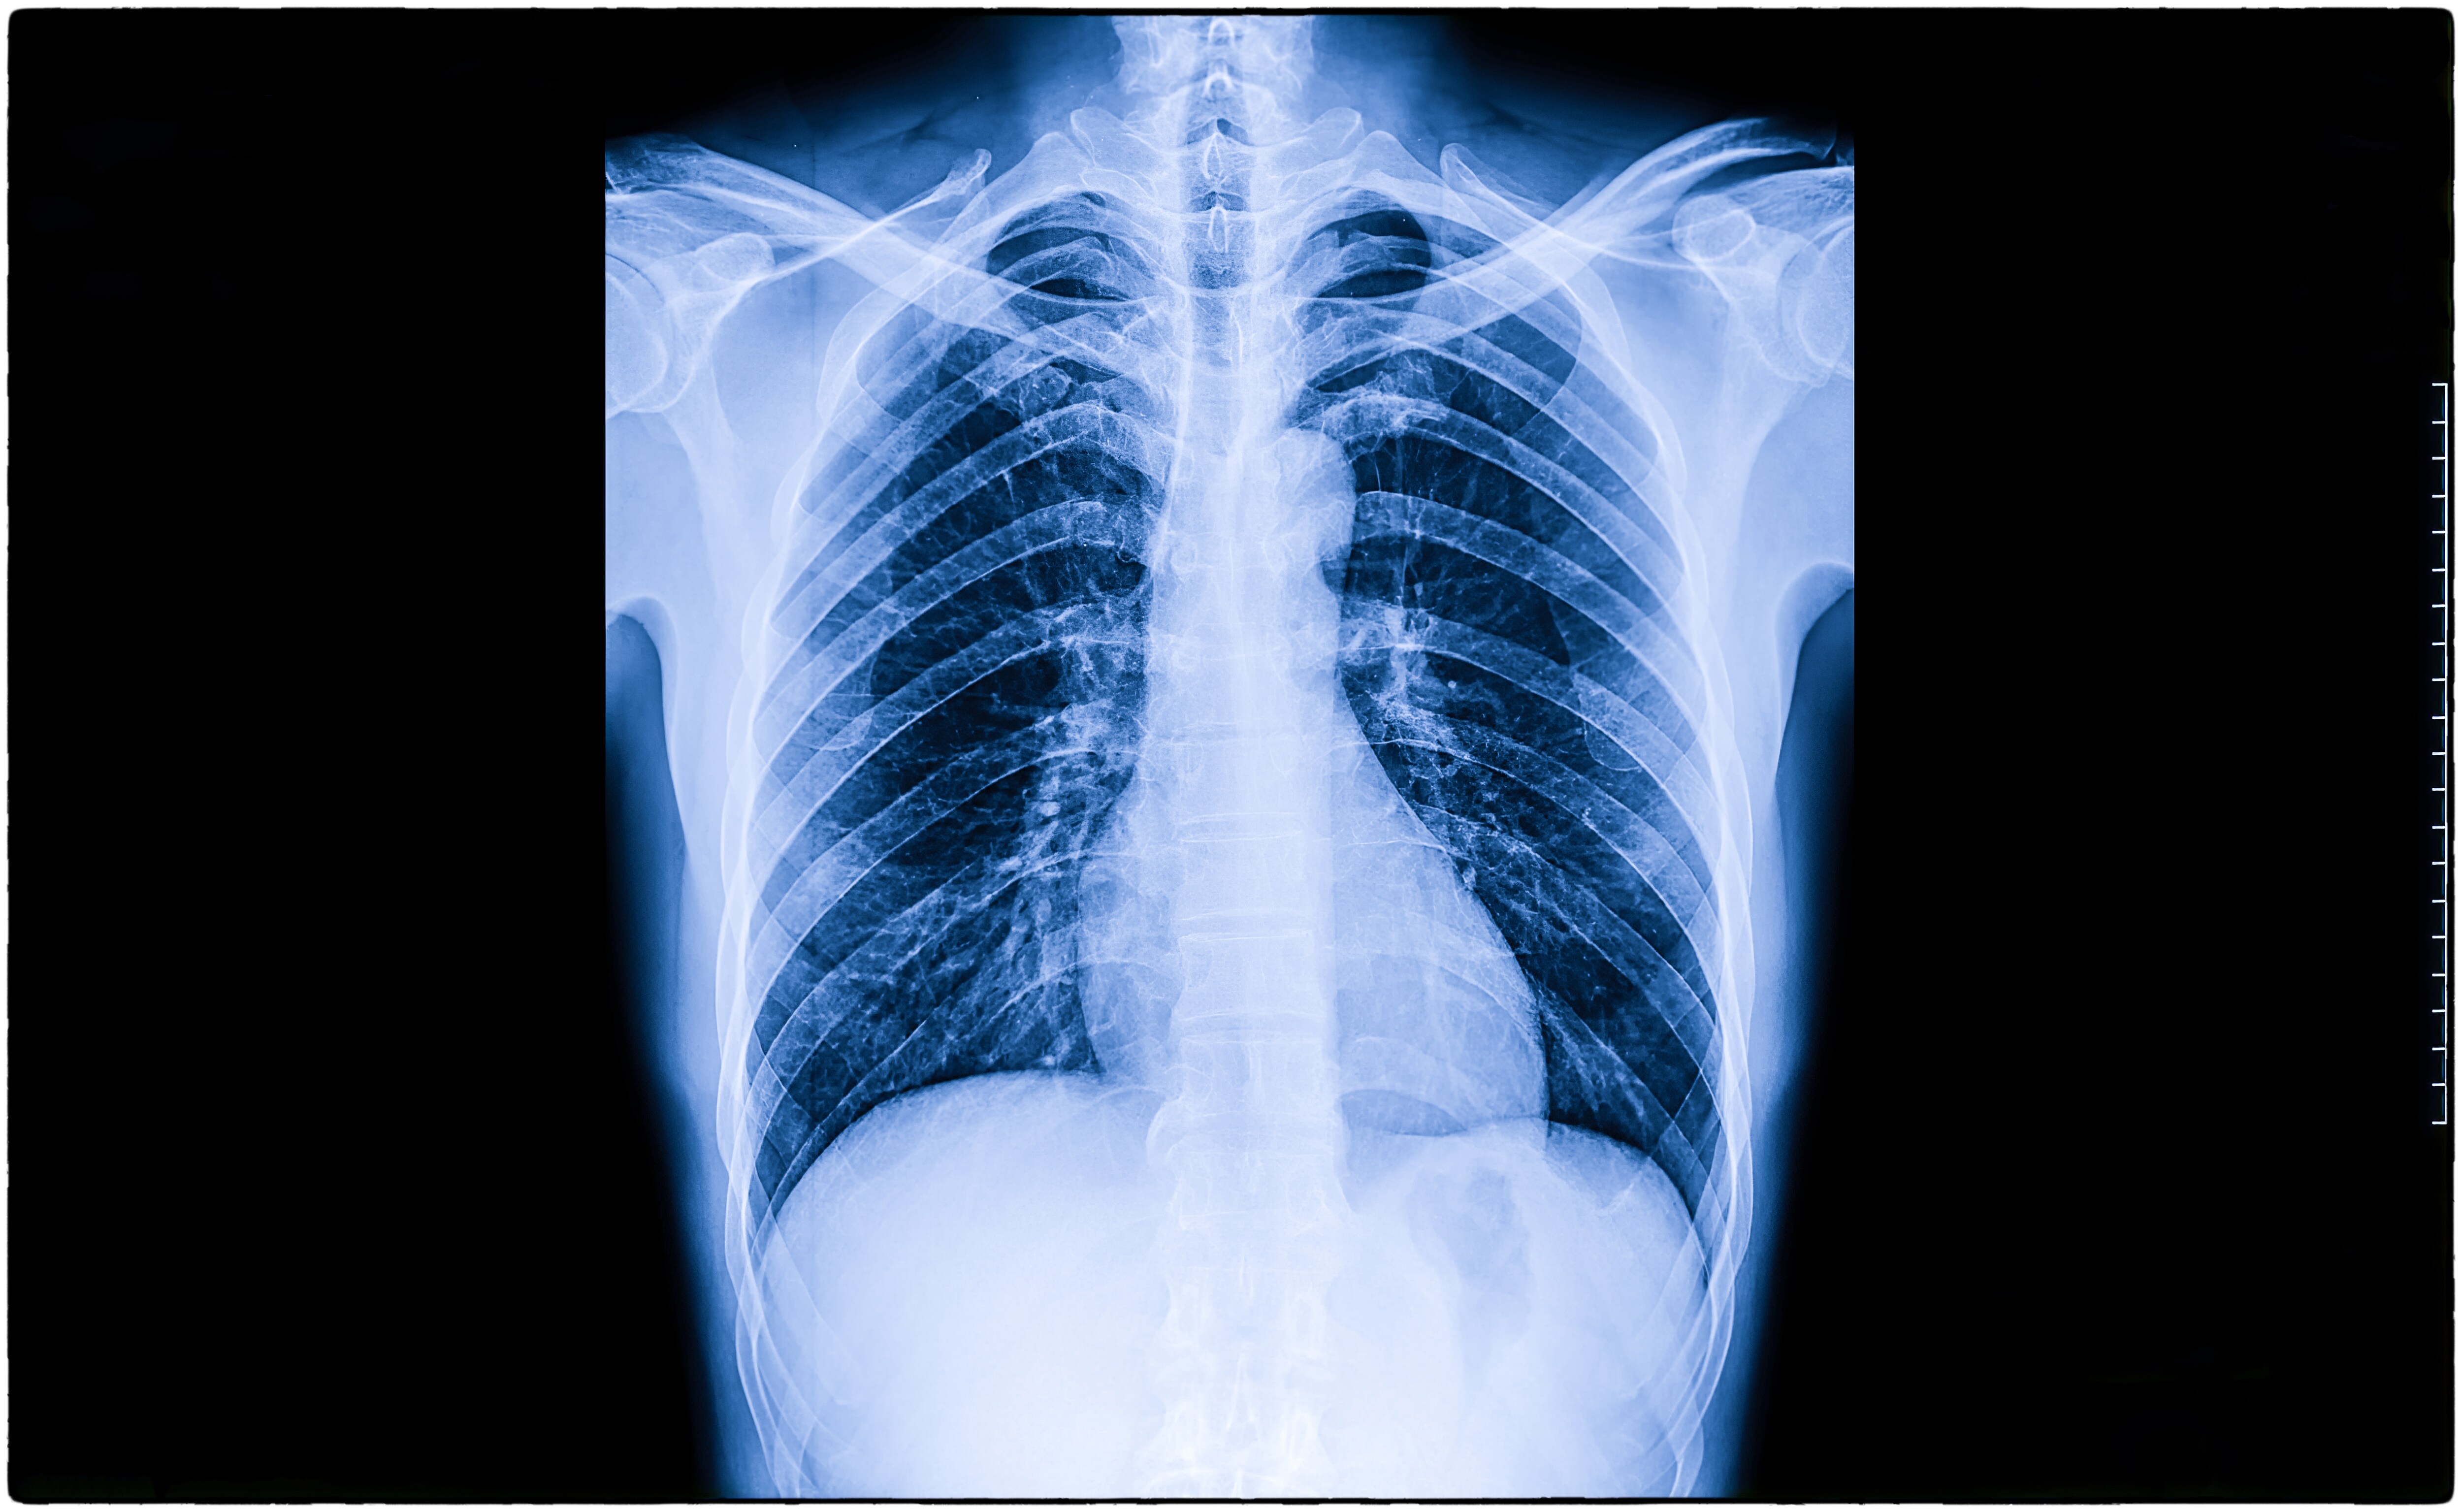

Once thought of as diseases of old age, lung cancer, Chronic Obstructive Pulmonary Disease and tuberculosis are now being seen earlier in life. (Photo: Envato)

Once thought of as diseases of old age, lung cancer, Chronic Obstructive Pulmonary Disease and tuberculosis are now being seen earlier in life, raising fears of a demographic and economic disaster.